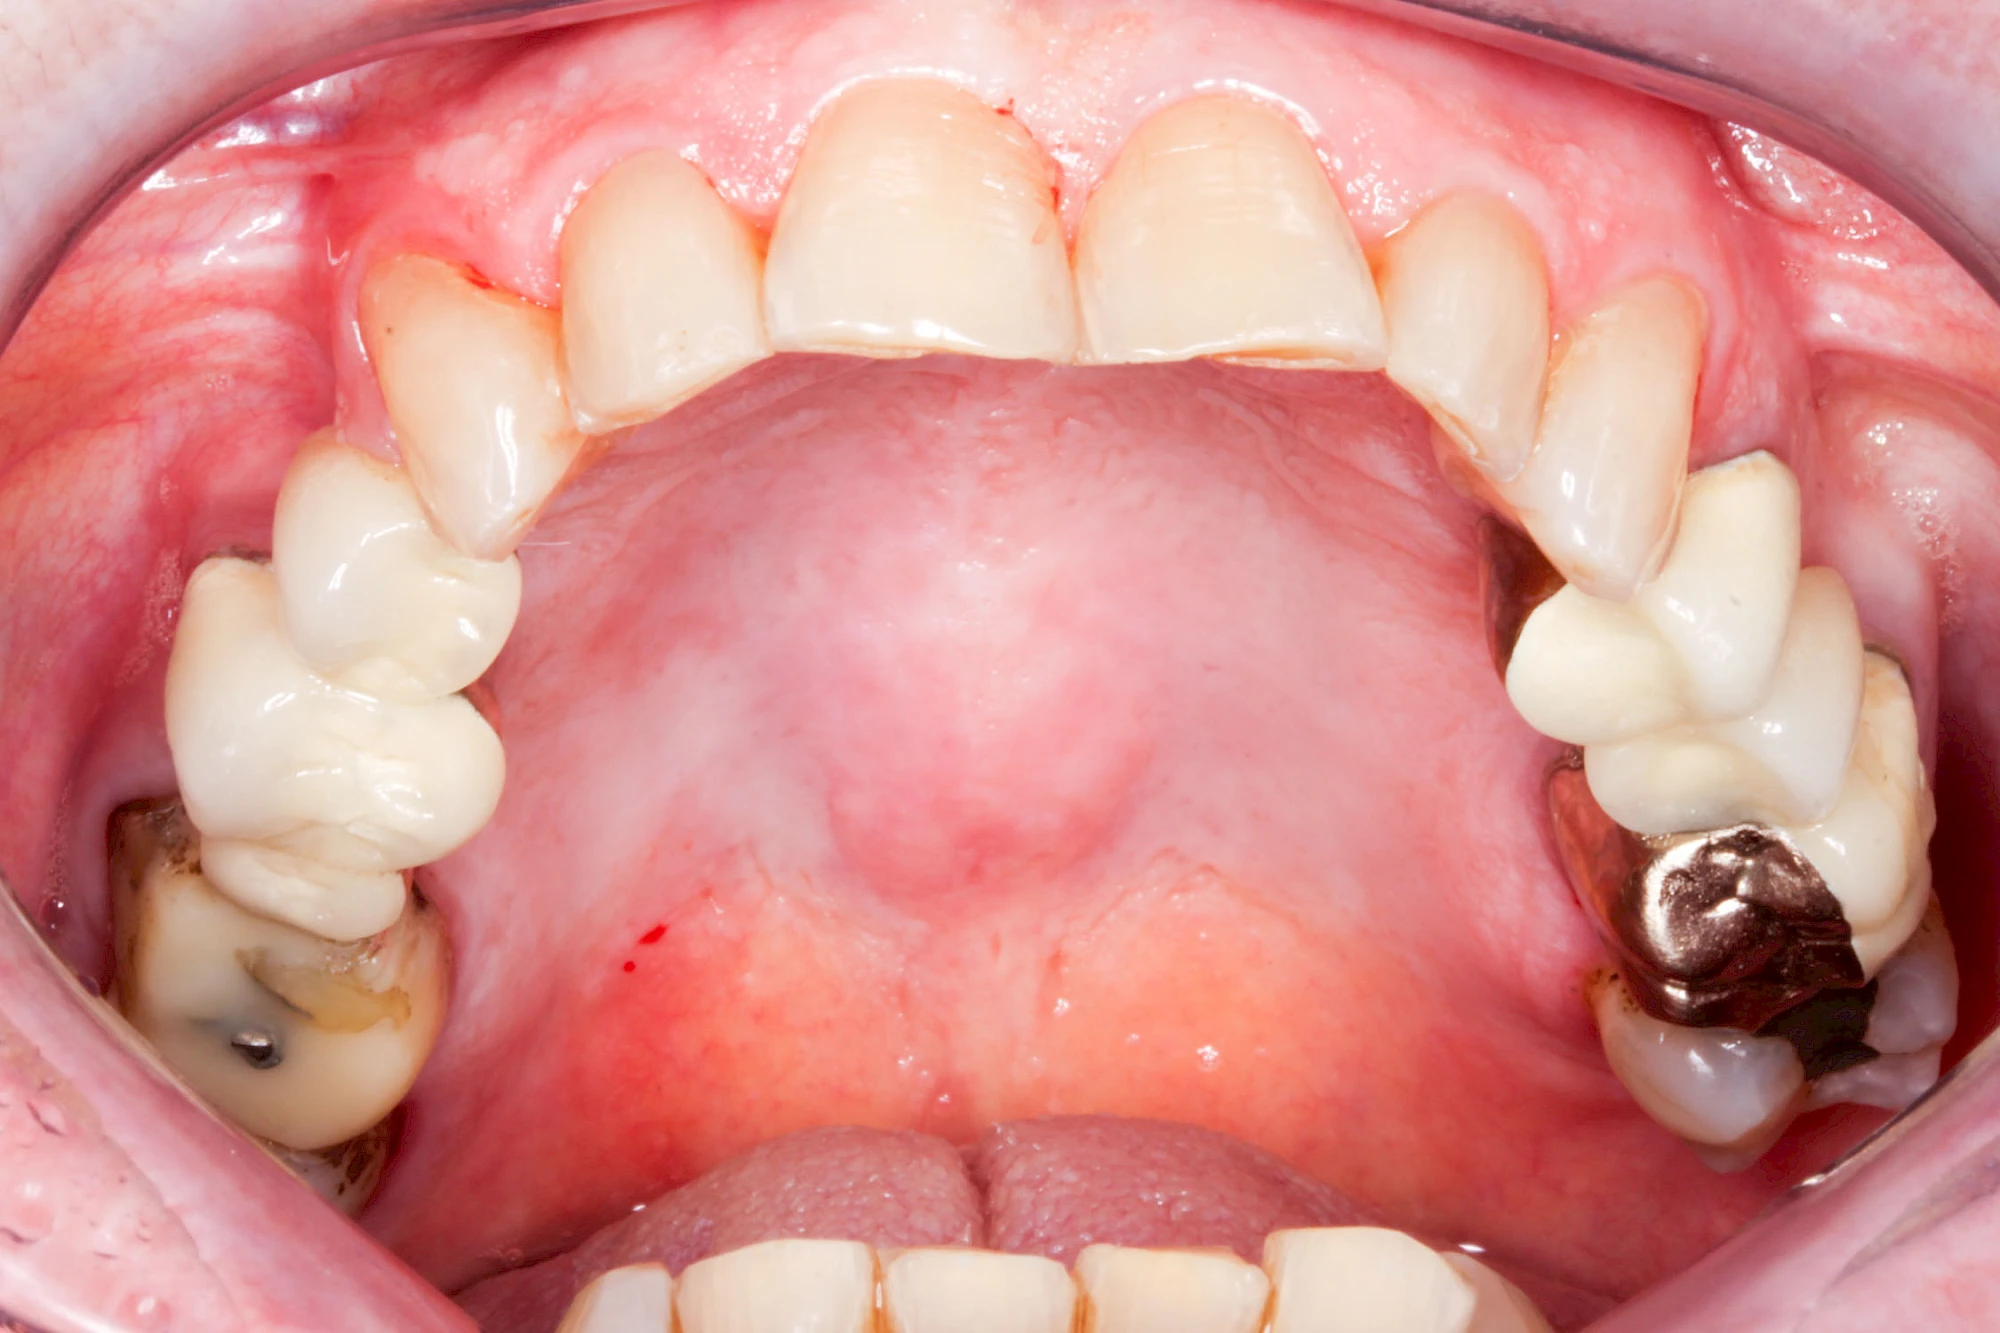

Gehen die Zähne verloren, baut häufig auch der Kieferknochen ab (Knochenschwund). Die Geschwindigkeit und das Ausmaß des Knochenschwundes ist von vielen Faktoren abhängig. Neben der genetischen Veranlagung spielen auch Überbelastungen in Folge, z. B. bei ständigem Knirschen oder Pressen, eine Rolle. Auch wenn Zahnprothesen Tag und Nacht getragen werden, kann die ständige Belastung der Schleimhäute und des Knochens den Knochenschwund beschleunigen.